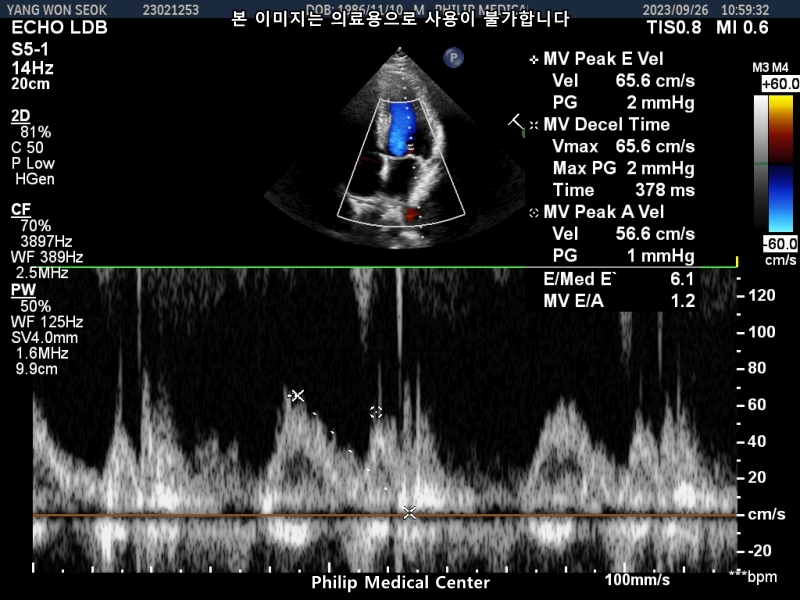

심장초음파는 경미한 폐동맥 판막역류소견과 심전도 검사결과 비특이적 ST-T파 이상소견이있었습니다.

• 3번 째 사진